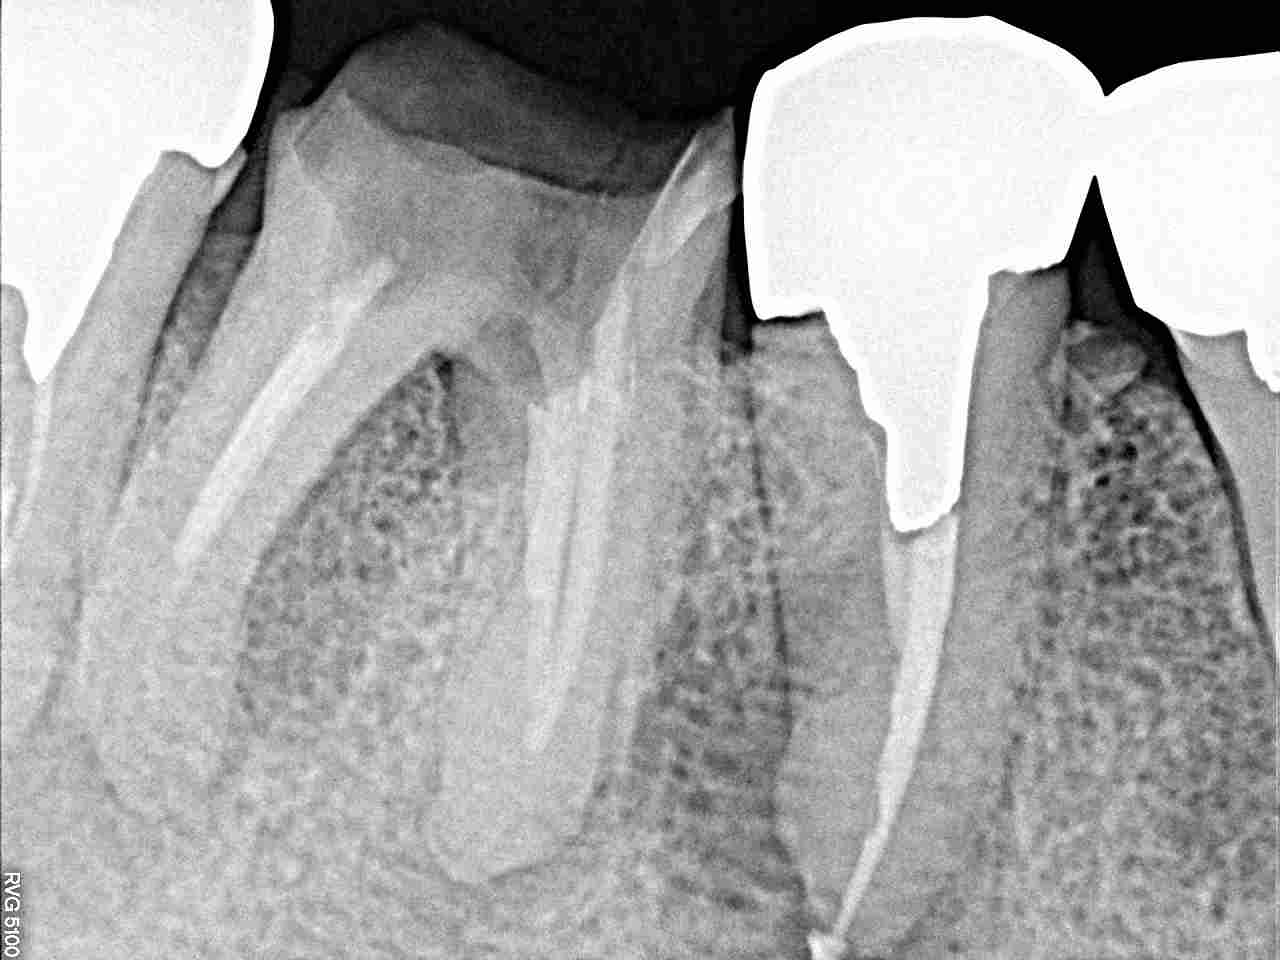

右下6番の抜歯後の早期インプラント埋入 5mmの13㎜というインプラントサイズを埋入しています|お知らせ |広島市安佐南区の歯科医院 右下6番の抜歯後の早期インプラント埋入 5mmの13㎜というインプラントサイズを埋入しています トップ お知らせ・ブログ お知らせ 右下6番の抜歯後の早期インプラント埋入 5mmの13㎜というインプラントサイズを埋入しています 右下6番の抜歯後の早期インプラント埋入 5mmの13㎜というインプラントサイズを埋入しています 右下6番の破折に伴うコアごと脱離 中は大きく虫歯 破折線になります デンタルレントゲンでも骨吸収が進んでいます まずは抜歯を行い2か月後に埋入していきます 開けてみるとこんな感じにおなります インプラント埋入しています このように埋入しています Web診療予約 初めての方へ 選ばれ続ける理由 院内設備について 歯が痛いしみる一般歯科 歯がぐらぐらする歯周病 健康な歯を保ちたい予防歯科 子供の虫歯予防をしたい小児歯科 銀歯をセラミックに審美歯科 白い歯を目指しませんか?ホワイトニング 矯正専門医がいるので安心矯正歯科 抜けた歯を補いたいインプラント・入れ歯 医院案内 スタッフ紹介 メリィハウス歯科クリニックオフィシャルホームページ ラベンダー歯科クリニックオフィシャルホームページ お知らせ・ブログ ホーム 診療科目 一般歯科 歯周病治療 予防治療 小児歯科 審美治療 ホワイトニング 矯正歯科 入れ歯・インプラント マウスピース矯正 初めての方へ 院長・スタッフ 設備紹介 医院案内・アクセス メニューを閉じる